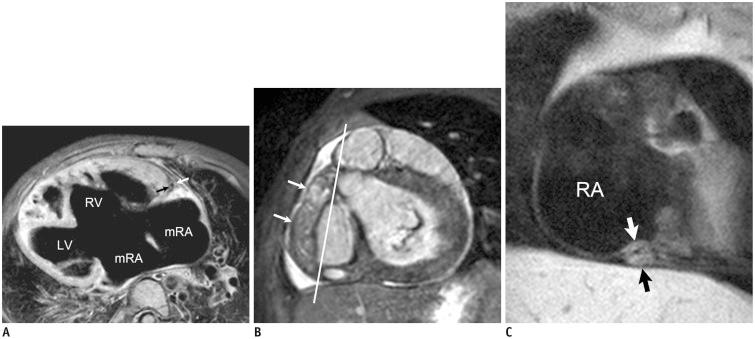

Coronary artery problems in children usually have a significant impact on both short-term and long-term outcomes. Early and accurate diagnosis, therefore, is crucial but technically challenging due to the small size of the coronary artery, high heart rates, and limited cooperation of children. Coronary artery visibility on CT and MRI in children is considerably improved with recent technical advancements. Consequently, CT and MRI are increasingly used for evaluating various congenital and acquired coronary artery abnormalities in children, such as coronary artery anomalies, aberrant coronary artery anatomy specific to congenital heart disease, Kawasaki disease, Williams syndrome, and cardiac allograft vasculopathy.